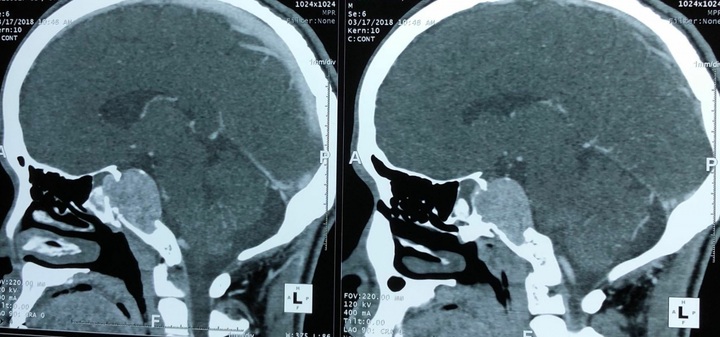

Tuy nhiên, ngay khi chỉ định chụp cộng hưởng từ để phân biệt khối u với các dây thần kinh đã gặp trở ngại do khối u quá lớn, không thể đưa vào lồng chụp.